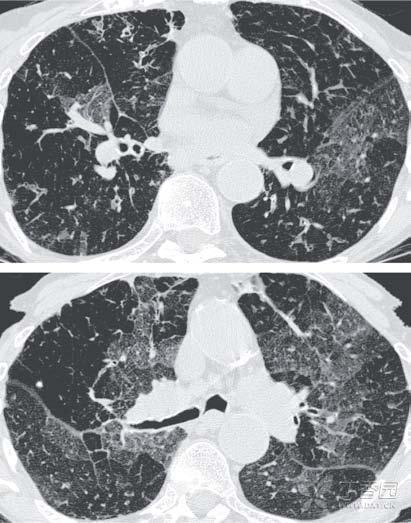

早在十年前,人们就对这个物质闻声色变,在当时,它曾导致了一个严重的肺部疾病——

闭塞性支气管炎。

闭塞性支气管炎是一种罕见、致命且不可逆的阻塞性肺病,

若患上了这种疾病,别说抽烟了,可能很长一段时间都要在抽血中度过了。